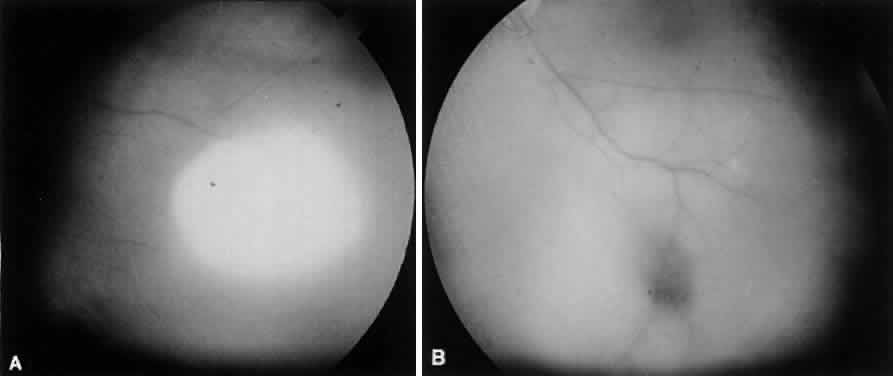

The choroid has a particular propensity for involvement by TB. Choroidal granulomas can be solitary or—as in miliary TB—multiple, causing a disseminated choroiditis. Choroidal granulomas are yellowish-white nodules with indistinct borders, ranging in diameter size from 0.5 mm to 2 cm. They may be seen in patients without active systemic disease (Figs. 4 and 5). Although A-scan findings are variable, B-scan typically reveals a solid elevated choroidal mass with an absent scleral echo due to absorption by inflammatory cells.55 Fluorescein angiography generally shows early hyperfluorescence with leakage at the margins and late central leakage. After treatment, there may be loss of early hyperfluorescence and late staining. Choroidal neovascularization can occur.55–57 Endobiopsy has been performed safely for diagnosis.58

Fig. 4. Tuberculous choroiditis does not have a pathognomonic appearance. The presenting symptoms usually are blurred vision and floaters. A. This patient had a 2-month history of decreased vision and presented with a large choroidal infiltrate. Systemic TB was proved by culture of Mycobacterium tuberculosis. B. The lesion responded dramatically to systemic antituberculous medications.

Fig. 5. Latent choroidal tubercle in a patient with multidrug resistant TB.